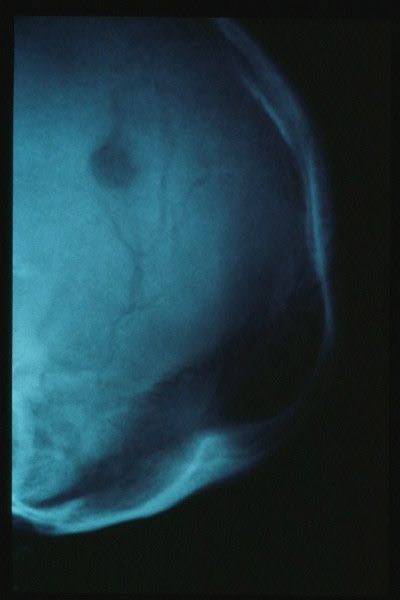

Hiperostosis craneal.